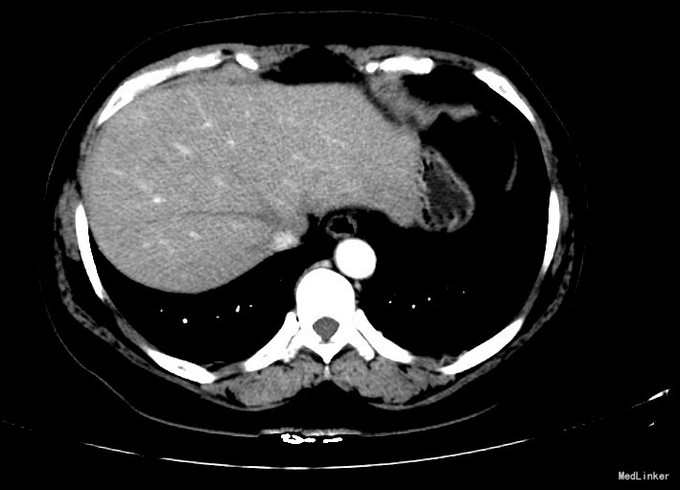

查体:体格检查:体温36.4℃,脉搏72次/分,呼吸18次/分,血压120/70毫米汞柱,神志清,状态可,皮肤及巩膜无黄染,手掌赤痕阳性,红丝赤缕阴性,心肺听诊未闻异常,腹软,无压痛,肝脾肋下未及,移动性浊音阴性,双下肢无浮肿,扑翼样震颤阴性,舌象:舌淡红、苔薄白,脉象:弦脉。 化验:血细胞分析:白细胞计数 6.3 10^9/L、红细胞计数 4.73 10^12/L、血小板计数 175.0 10^9/L、血红蛋白 156 g/L,肝功酶谱:丙氨酸氨基转移酶 22 U/L、碱性磷酸酶 84 U/L、白蛋白 43.8 g/L、总胆红素 13.3 umol/L,甲胎蛋白测定:甲胎蛋白 182.80 ng/mL 彩超:符合慢性肝损伤,肝右叶高回声性质待定0.7cm 肝弹性测定:CAP 252 E 6.9 增强CT:脾大,肝硬化?肝内多发RN,大小约1.2cm,Ⅱ段结节合并Ca变可能性大

诊断:1.乙肝肝硬化 活动性 代偿期 C-P分级 A级 5分 2.肝占位(不除外HCC) 治疗:患者乙肝肝硬化患者,多次于我院中医科住院治疗,本次住院期间中医理疗、抗病毒治疗,查甲胎蛋白增高,并且增强CT发现肝内可疑病灶,考虑原发性肝癌可能性大,于局麻下行TACE治疗,术中诊断为原发性肝癌以微导管超选S2段肝动脉一分支,造影明确为肿瘤供血动脉,注入混悬液(碘化油5毫升+雷替曲塞2毫克)3.2毫升,栓塞微球0.1毫升。

术后患者略乏力,食欲可,二便正常。 查体:神志清,状态可,皮肤及巩膜无黄染,有肝掌,无蜘蛛痣。心肺听诊未闻异常,腹软,无压痛,肝脾肋下未及,移动性浊音阴性,双下肢无浮肿,扑翼样震颤阴性。足背动脉搏动良好。 化验肝功转氨酶略有上升,甲胎蛋白下降。 DSA下肝动脉造影,即是肝癌有效的诊断手段,又是有效的治疗手段,如本例患者,在术中诊断为原发性肝癌的同时,及时进行治疗。TACE创伤小、恢复快、效果较好,是有效的治疗手段